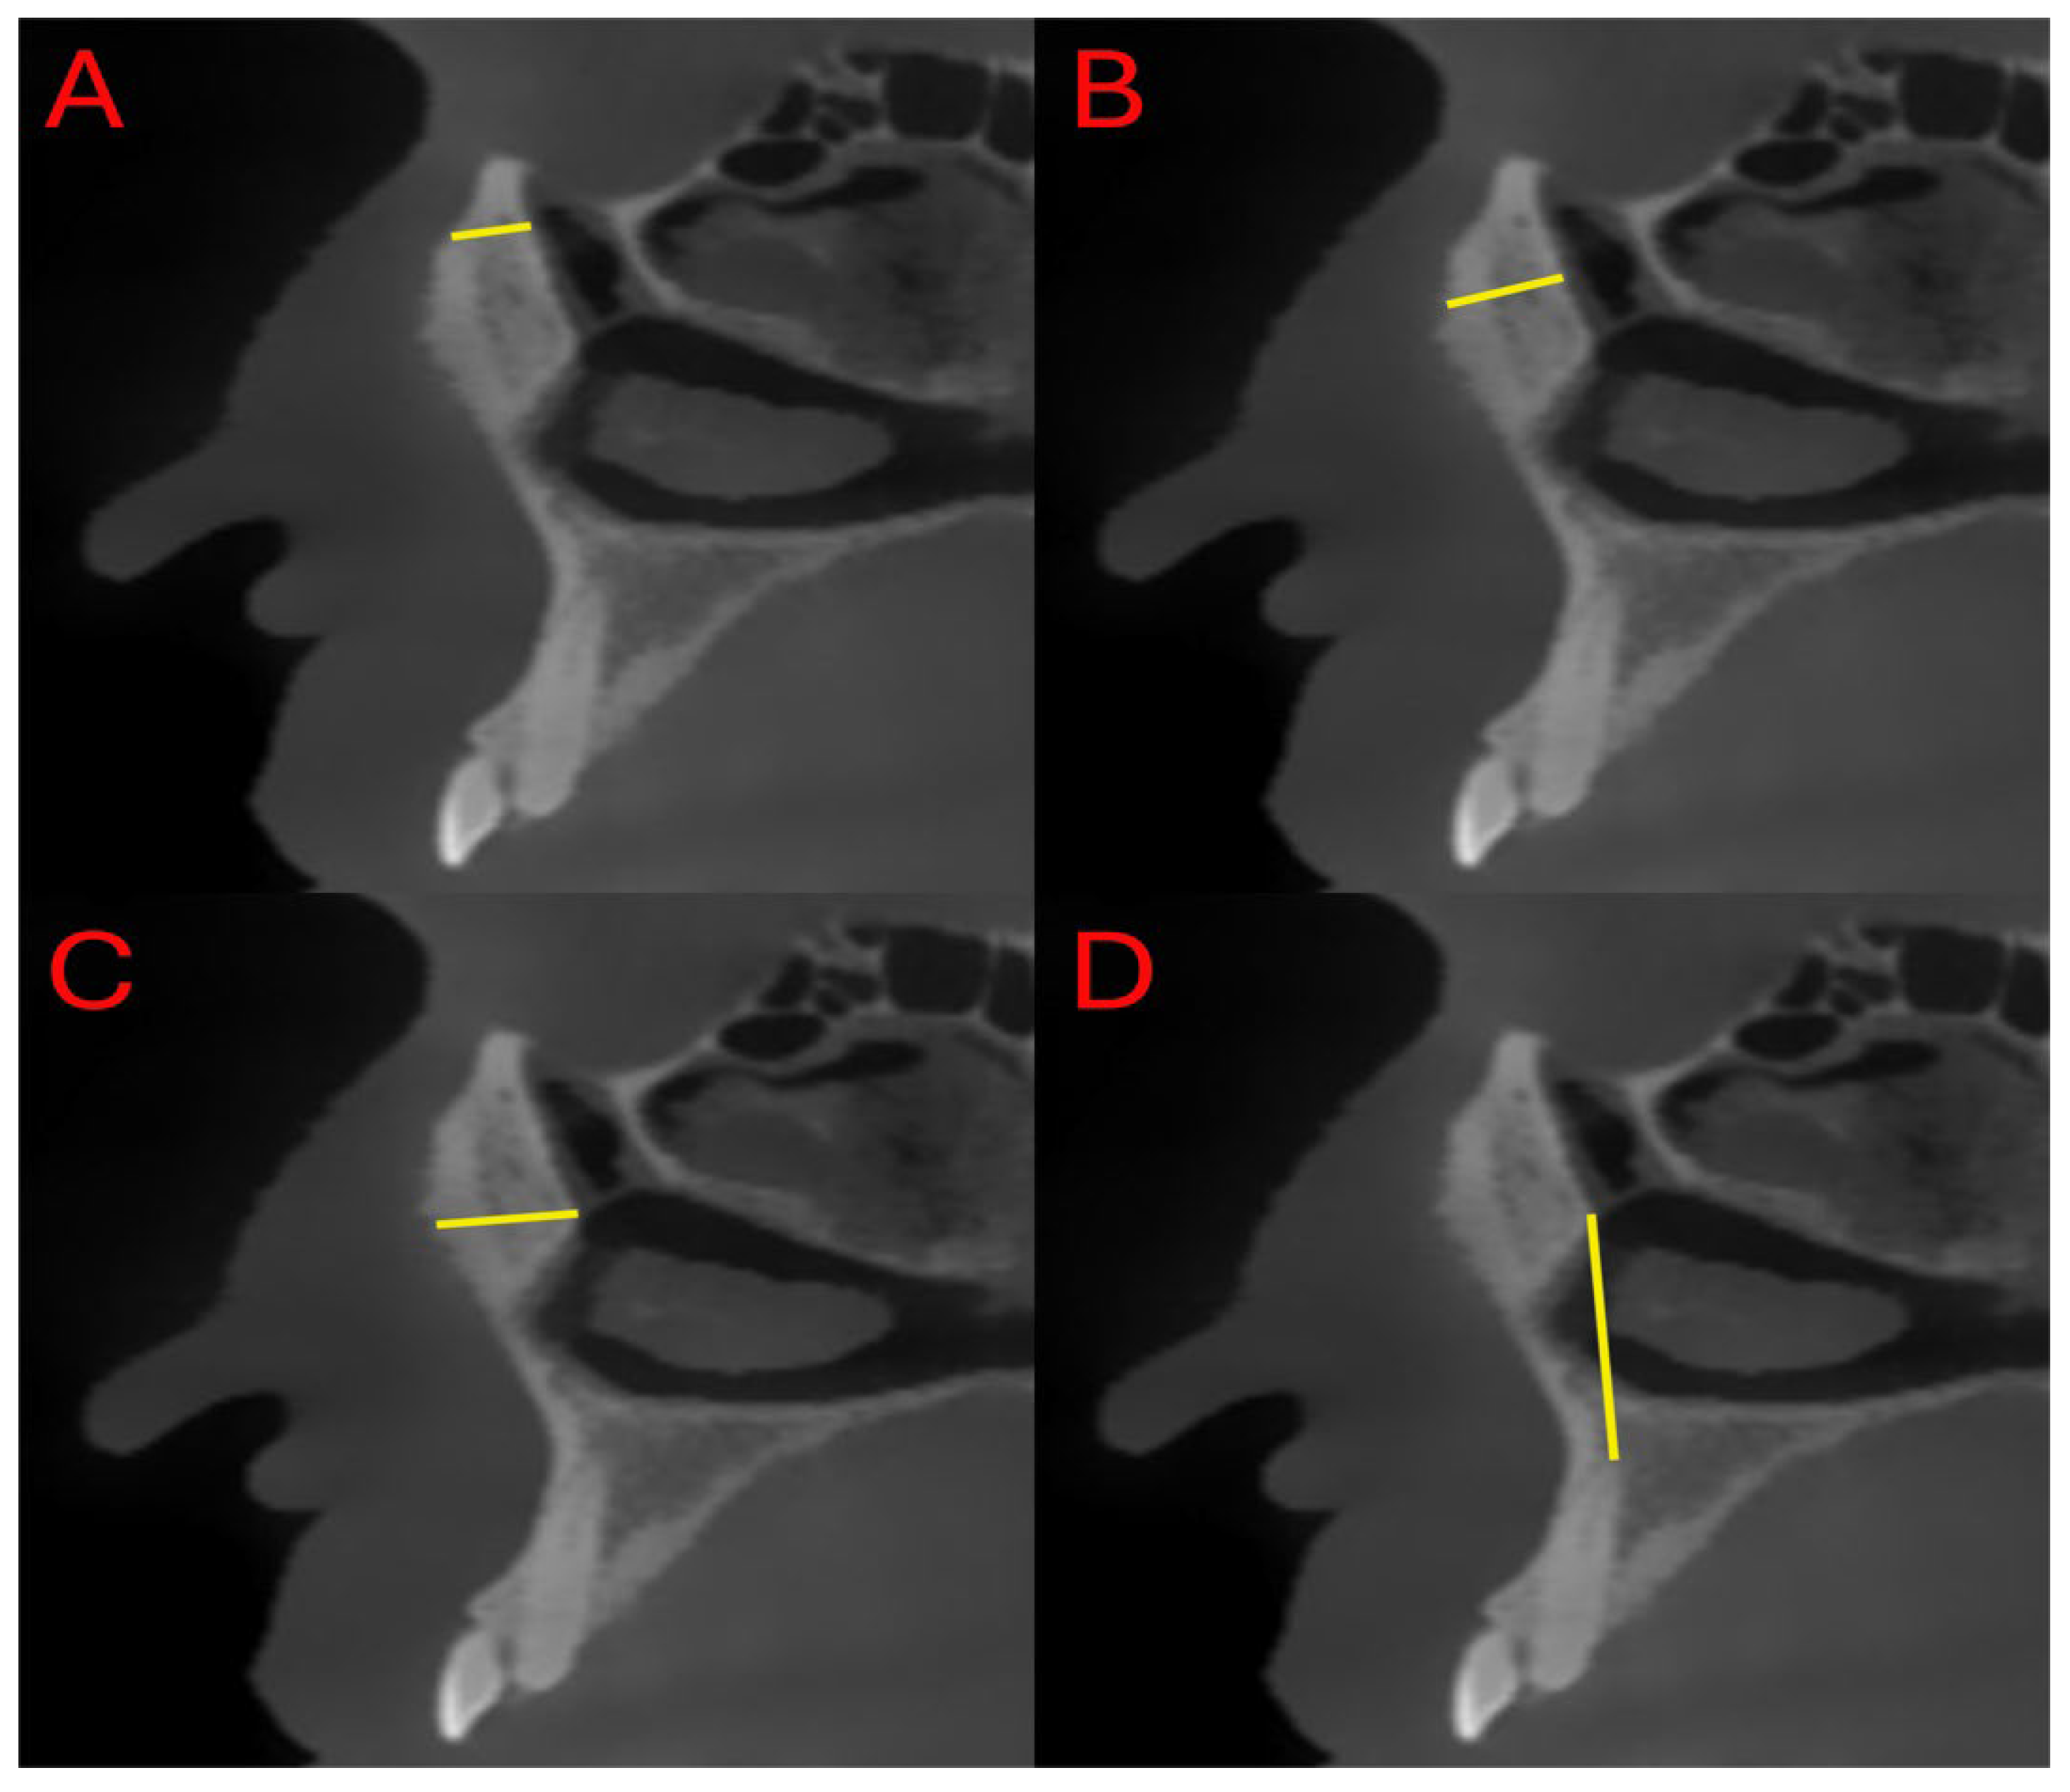

- Distance between the superior ostium (S) of the nasolacrimal canal and the anterior maxillary border (SL)

- Distance between the middle point (M) of the nasolacrimal canal and the anterior maxillary border (ML)

- Distance between the inferior ostium (I) of the nasolacrimal canal and the anterior maxillary border (IL)

- Distance between the canine apex (C) and the inferior ostium (I) of the nasolacrimal canal (IC)